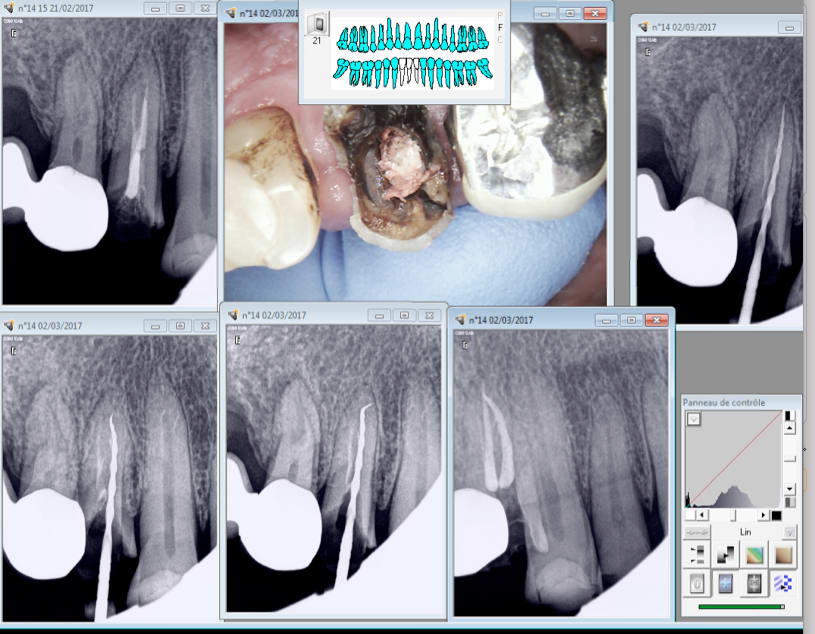

raison simple : tes deux canaux se rejoignent

il aurait fallu commener a obturer par l'autres canal qui allait au bout , parceque quand tu résinstrumentes un des deux (même pour recapituler) tu induis nécessairement une petite remontée de debis dans l'autre canal (c'est physique) qui peut bloquer ton cone, et ensuite le deuxième bute sur le premier

Les joies du RTE. -)

Bon la radio finale c'est bon. -)